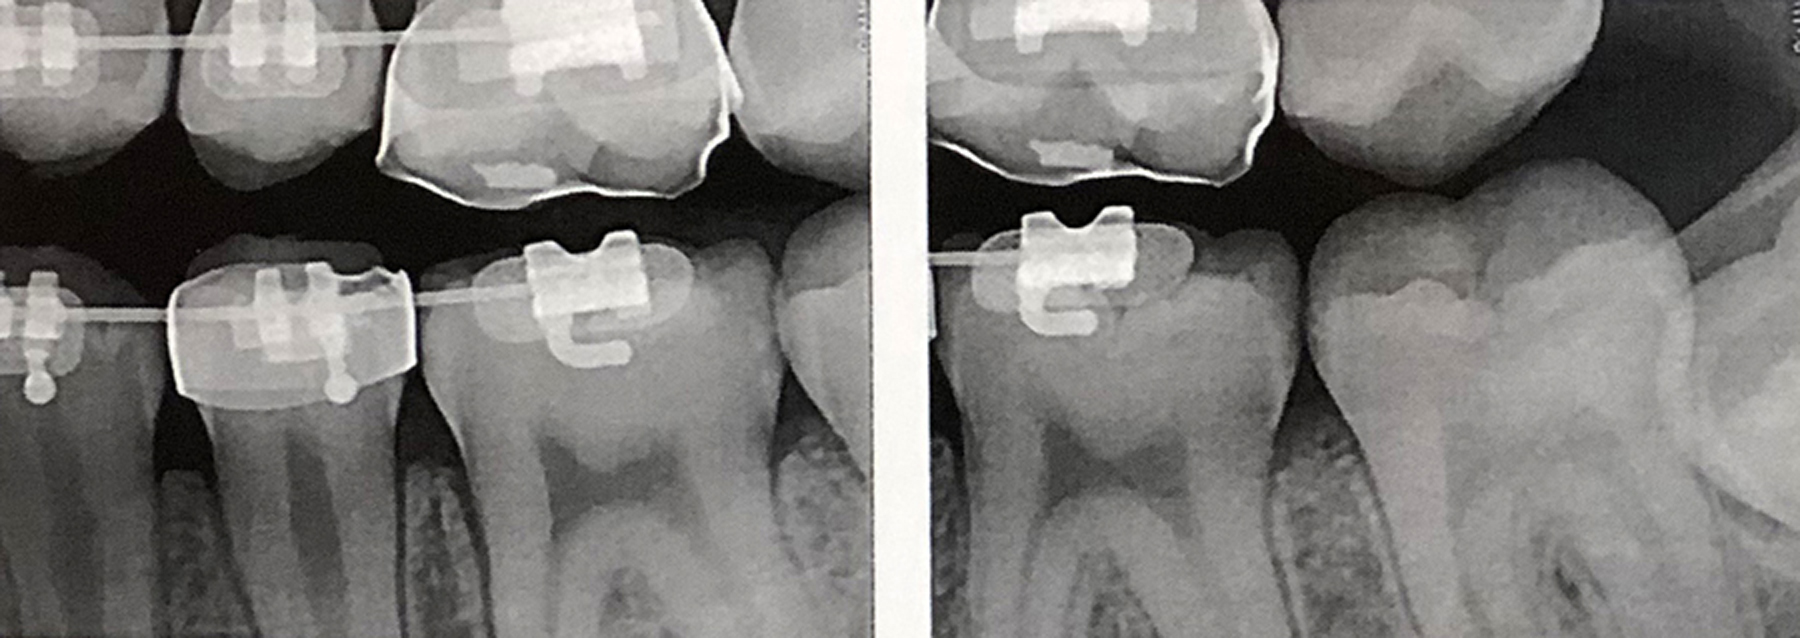

(20.) SDF proximal applications for small first and second molar caries lesions in teenage orthodontic patient, followed by preventive fluoride varnish cover of the area.

Figure 20

(21.) SDF proximal applications for small first and second molar caries lesions in teenage orthodontic patient, followed by preventive fluoride varnish cover of the area.

Figure 21

(22.) SDF proximal applications for small first and second molar caries lesions in teenage orthodontic patient, followed by preventive fluoride varnish cover of the area.

Figure 22